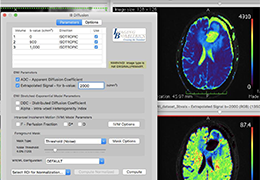

ART-Plan™ Artificial Intelligence Contouring